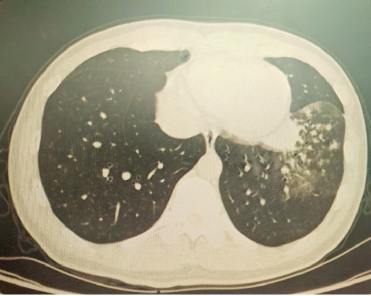

以上是他的胸部CT影像,主要表现为左下肺炎症,片絮影+磨玻璃影。

4月后再次复查胸部CT,提示病灶已经完全吸收。